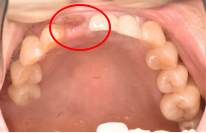

女性Sさん 50代(オールセラミック冠)

主訴

左上の差し歯がとれたままになっている。

治療内容

レントゲンを撮り詳しく診てみると、歯根が破折して保存することができず、抜歯する必要があることがわかりました。抜歯後、オールセラミックブリッジで補綴(欠損した部分を人工物で補う)しました。ブリッジの支台になっている後方の歯は、根尖性歯周炎(根の先端で問題を起こしている)でしたので、根管治療をしています。

所感

抜歯後、欠損部分を補う方法には、1本だけの部分入れ歯、ブリッジ、インプラントの3つの方法があります。この患者さんは、ブリッジを選択されました。メタルフリーの治療を希望されましたので、土台をファイバーコアにし、オールセラミックのブリッジをかぶせました。患者さんは、お口の中の金属を徐々に減らしていきたいということです。体全体の健康のことを考えると正しいことです。

オールセラミック冠(失活歯)1本:¥104,500(税込)

オールセラミック冠(生活歯)1本:¥93,500(税込)

ポンティック1本:¥93,500(税込)

合計:¥291,500(税込)

Before

After